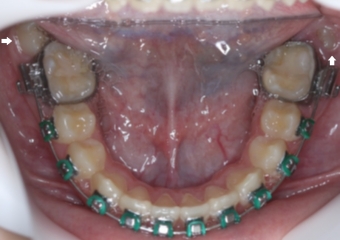

Oclusal inferior com segundos molares em posição inadequada - Clínica Cliniface

Oclusal inferior com segundos molares em posição inadequada